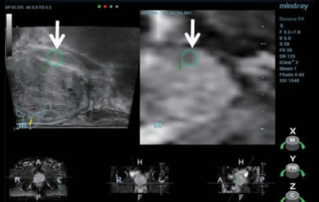

?? ?? ??? ?????(Endocavity volume convex array transducer)(DE10-3WU, Resona 7, ?????)? ??? ??? ???, ??? ?? 1/3 ?? ? ??(anterior vaginal wall)? ???? 18x14 mm ??? ?? ??(an ovoid-shaped formation) with a parietal fine suspension, ????? ??? ???? ??(non-displaced), ????,? CDI ??? ?? ?? ???? ????????. 3D ??? -? ??? ? ??(hyperechoic septa)? ?? ???? ??? ?? ??.

?? ??? ?? ???(Volumetric reconstruction)? ??? ??? ?? ??? ?? ??? ??? ? ??? ?? ??????? ??? ??? ??? ???.